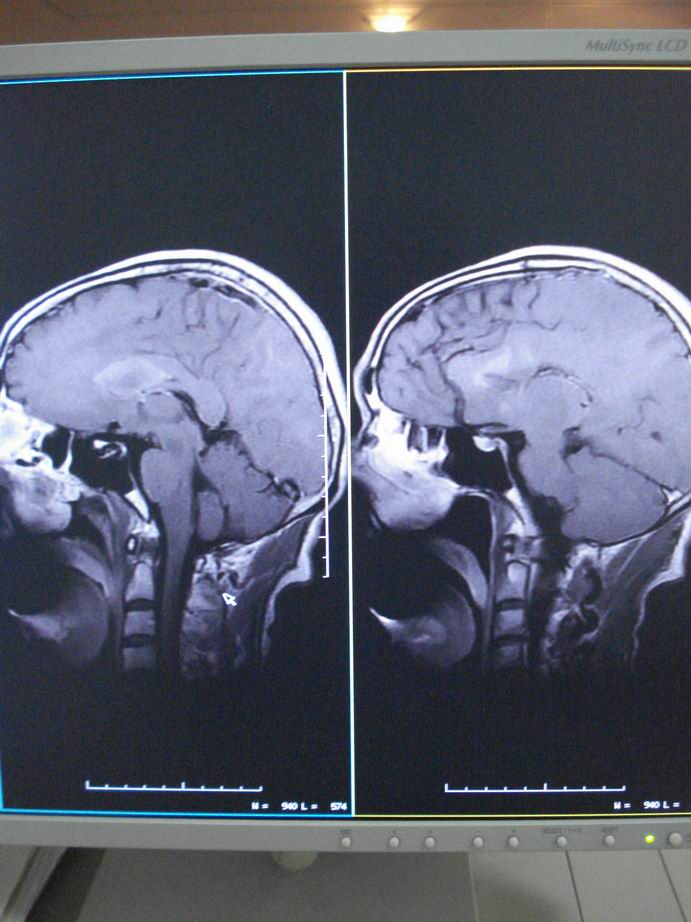

男60岁,左侧肢体乏力及精神异常10天,血压正常,血常规,肝肾功正常,腰穿无异常,请教颅内多发病灶,考虑什么?感染?肿瘤(转移性?)还是其它?

考虑为颅内多发转移瘤

脑内多发性转移瘤。

淋巴瘤较转移瘤可能大。